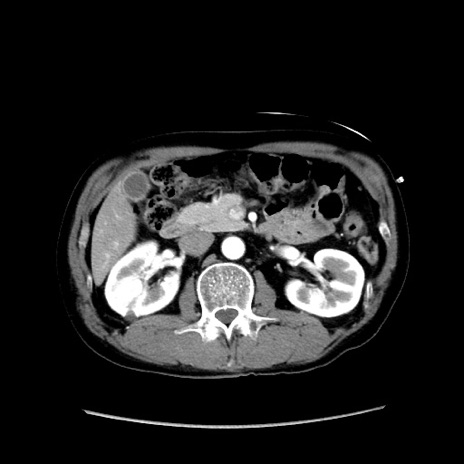

症例37(横断像)

【症例】40歳代 男性

【主訴】腹痛

【現病歴】4時間ほど前に電車に乗車中に臍部上より腹痛出現。徐々に増悪し起立困難となり、救急外来受診。生ものは数日食べていない。今朝お雑煮を食べた。

【身体所見】BT 36.8℃、BP 117/84mmHg、HR 91/min、SpO2 97%、苦悶様、腹部:臍上部広範囲圧痛あり、反跳痛±

【データ】WBC 8100、CRP 0.03